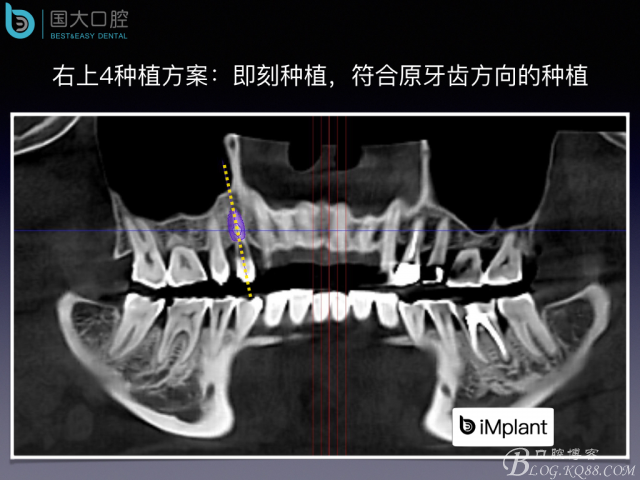

偏向顎側(cè)的即刻種植,應該如何修復?

20160820113239_39802.jpeg